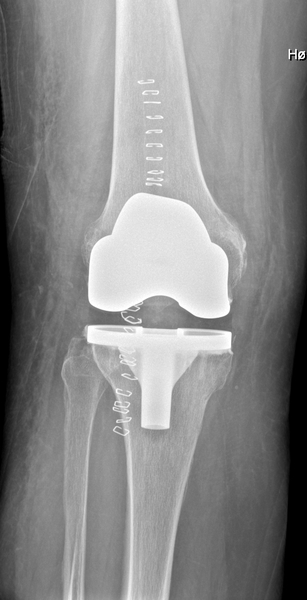

Knæ (postoperativ alloplastik)

AP

Thumb d4doc formularer upload 2014 11 kn c3 a6 20ap 20ligge 1 Thumb d4doc formularer upload 2016 11 kn c3 a6ap

Lejring:

Rygleje med benet let indadroteret, således femurkondylerne har samme afstand til pladen.

Rørkipning:

Centrering:

Lige distalt for patella. Vinkelret på tibiakomponenten.

Kriterier:

Komponenterne skal fremstilles symmetrisk og uden dobbeltkontur.

Bemærkning:

1. post-operative kontrol tages liggende. Det er vigtigt at alloplastikkomponenterne fremstilles optimalt, og derfor kan efterfølgende kontroller evt. tages i gennemlysning. Ved alloplastikknæ OBS sporing suppleres med axial patella (stående eller liggende).